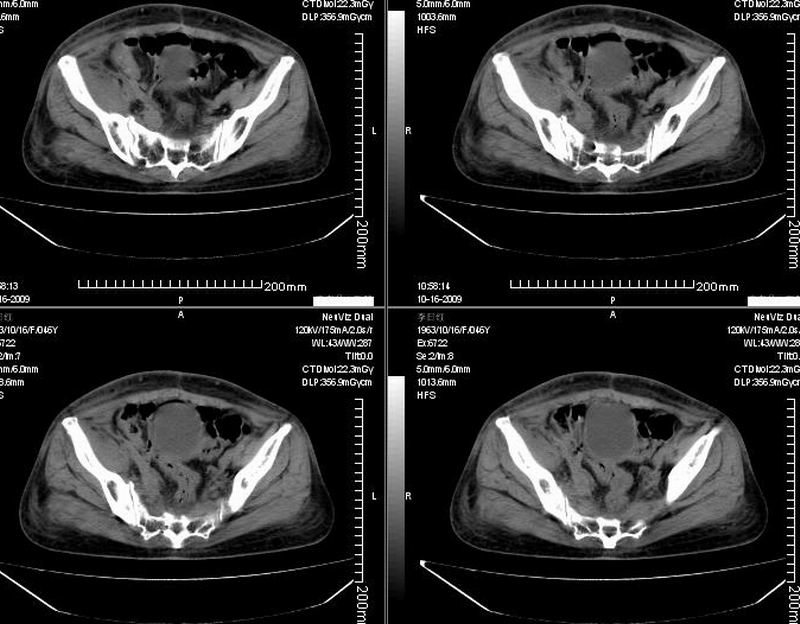

女:46y:一年前宫颈癌术后,现右下腹抚及肿块。

考虑宫颈癌术后复发周边侵犯/右中下腹及双侧腹股沟淋巴结转移。

考虑宫颈癌术后复发周边侵犯并右中下腹转移灶及双侧腹股沟淋巴结转移。